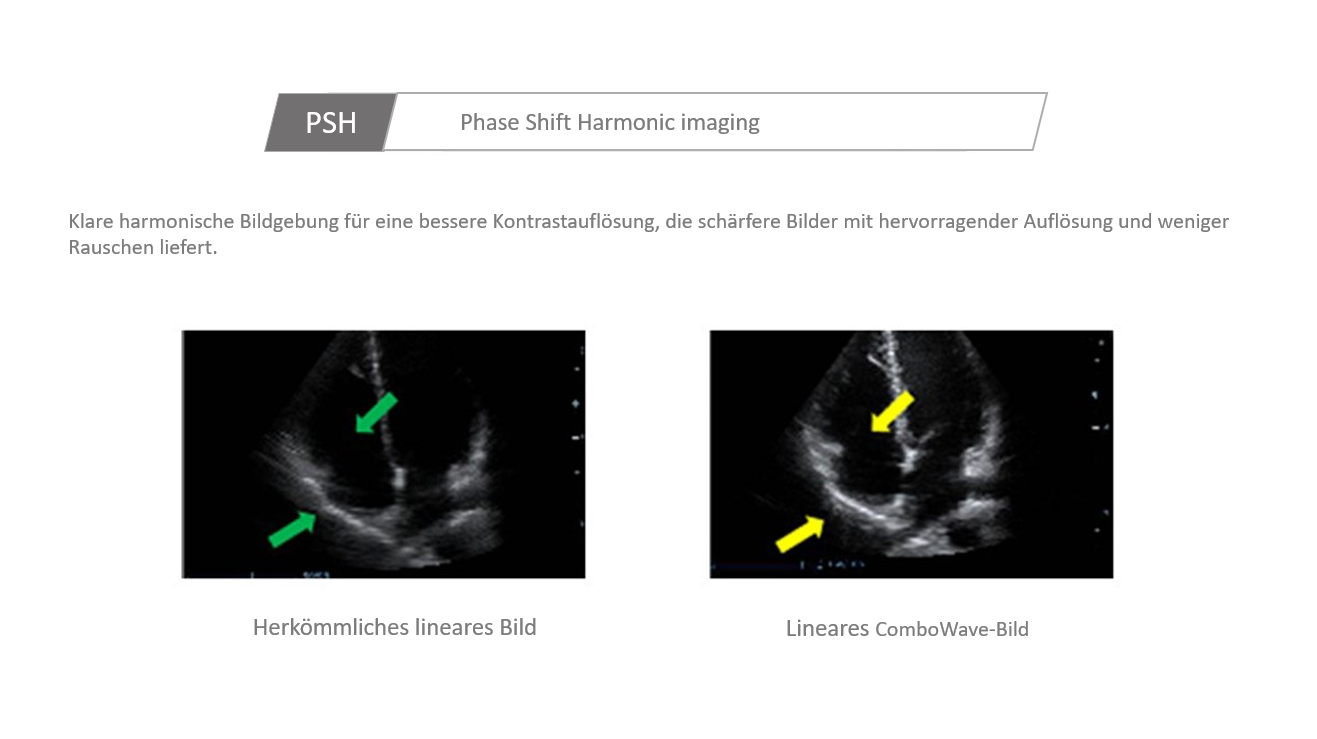

Der Einsatz anerkannter Bildgebungstechnologien macht das DC-30 mit Full HD sehr leistungsstark und hochwertig. Sie sind erfolgreich aus etablierten Ultraschallsystemen migriert worden. Eine clevere Kombination von Ultraschallsonden mit spezialisierten Schallk?pfen unterstĂŒtzt erstklassige Ergebnisse in einem breiten Anwendungsspektrum. Mit Hilfe der Breitband-Schallk?pfe l?sst sich eine Vielzahl an Patiententypen erfolgreich untersuchen. Diese bew?hrten Ultraschalltechnologien sorgen fĂŒr eine h?here Diagnosequalit?t:

- PSH (Harmonic Imaging mit Phasenverschiebung)